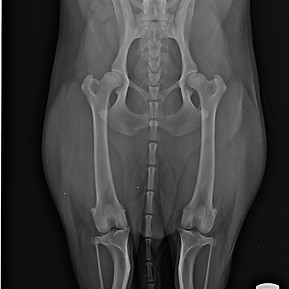

I migliori specialisti in diversi settori sono a lavoro per voi. Ci occupiamo di neurologia, diagnostica per immagini, riproduzione, genetica, animali non convenzionali, dermatologica, ortopedia, chirurgia, oftalmologia…in poche parole abbiamo a cuore la salute e la felicità del tuo pet.